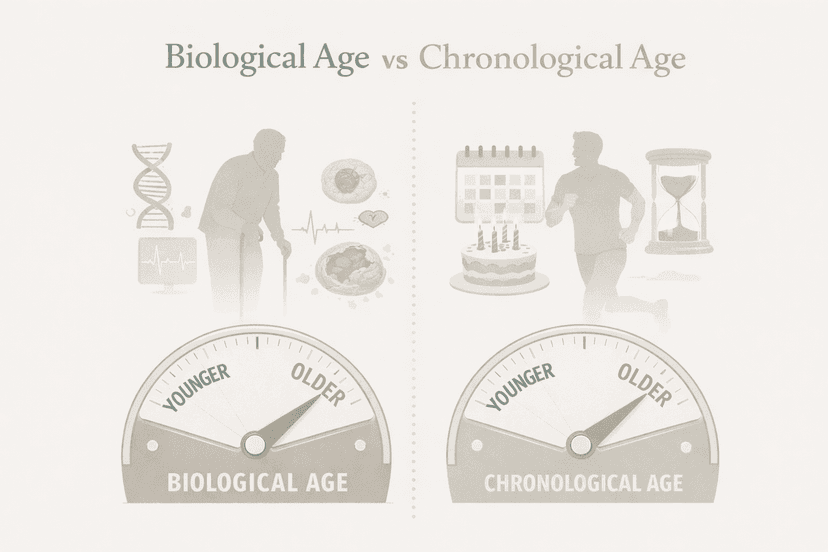

Most of us know our age without thinking twice. It’s the number tied to our birthday and the one that shows up on forms, health records, and insurance documents. This…